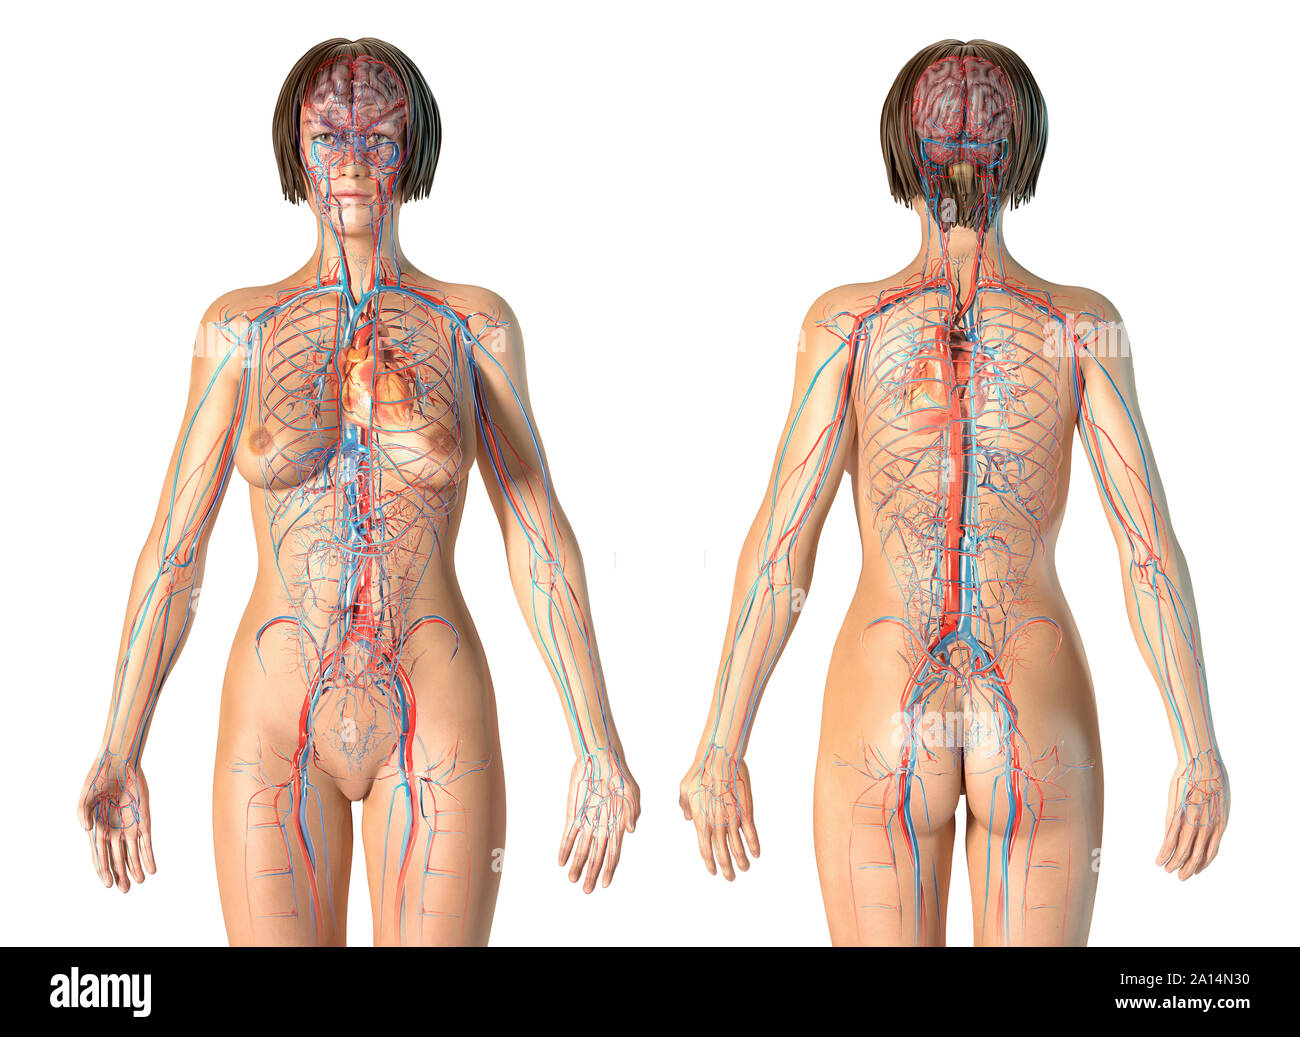

Анатомия человека: кровеносная система и её связь со скелетом